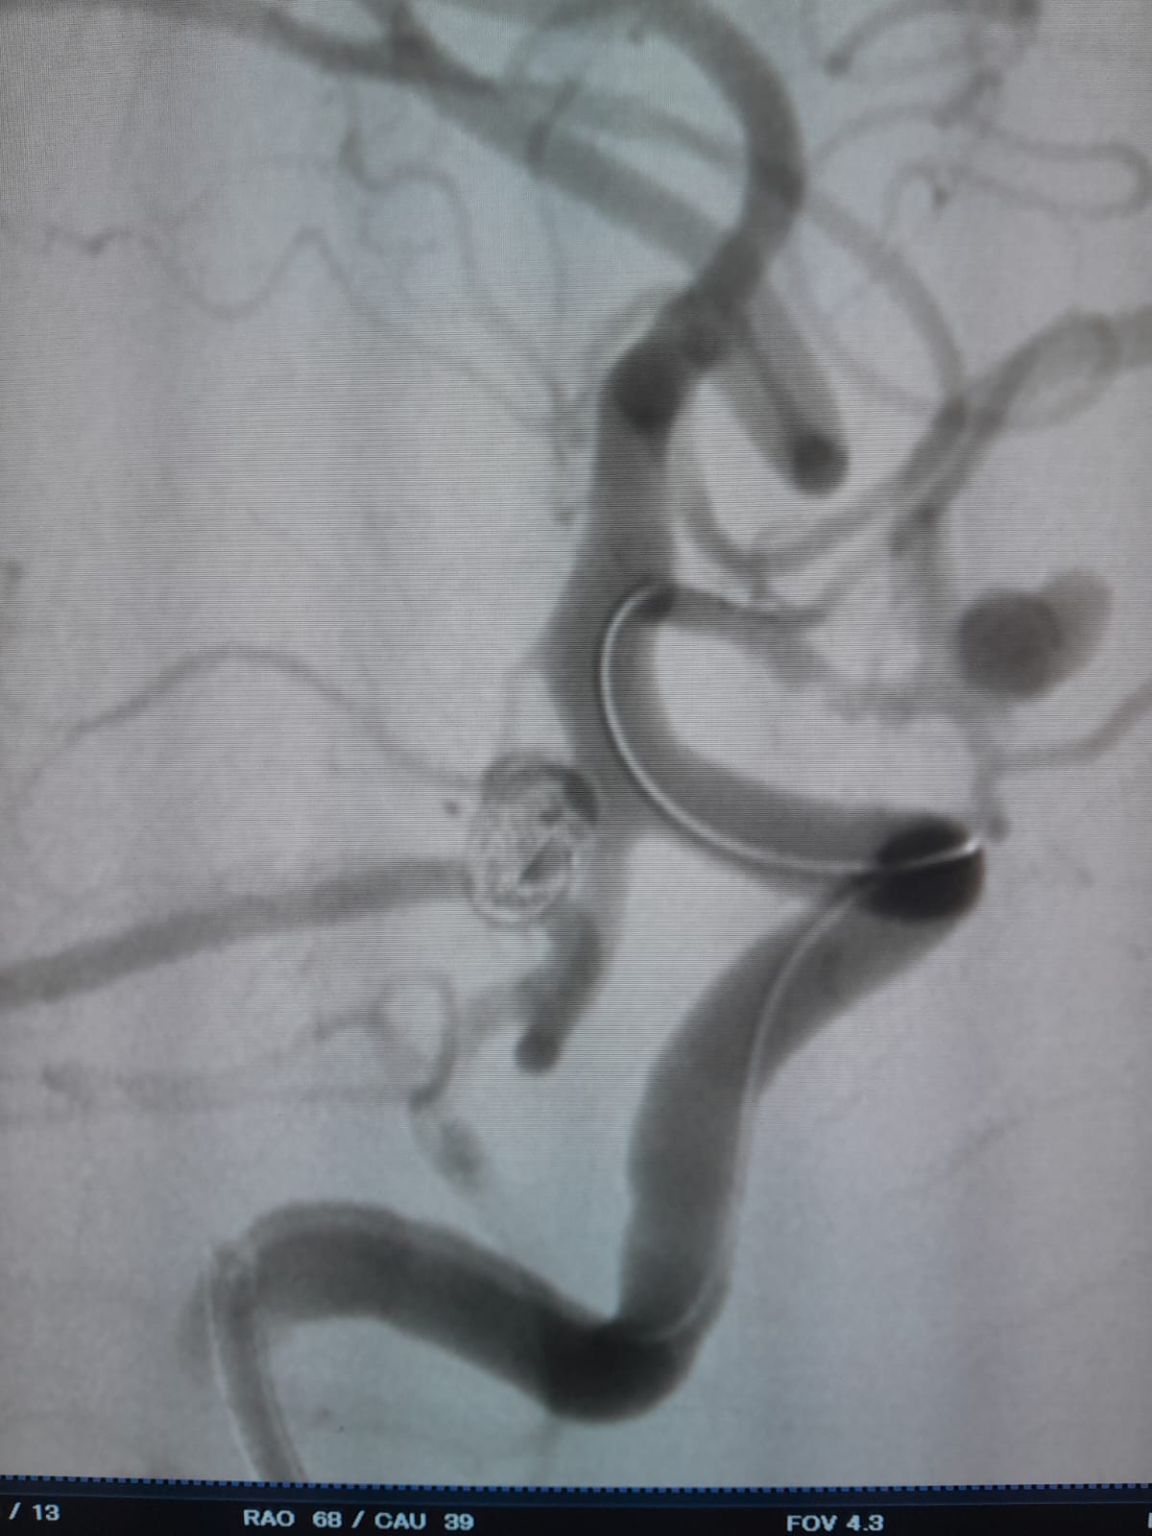

Le patient a été diagnostiqué avec un anévrisme sacculaire de l'artère communicante antérieure (AComA) nouvellement découvert et un anévrisme de l'artère communicante postérieure (PComA) qui avait été précédemment traité avec l'embolisation de la bobine. L'imagerie de suivi a révélé un remplissage résiduel dans l'anévrisme PComA, nécessitant une intervention supplémentaire.

Anévrisme de l'artère communicante postérieure (retraitement)

Au cours du suivi, un remplissage résiduel a été noté dans l'anévrisme de l'artère communicante postérieure précédemment traité. L'équipe a réaccédé au site en utilisant Frepass®Microcathéter jetable (TJMC18 Plus) et a déployé avec succès un Nuva®Déviateur d'écoulement (TJED-D-4.5-16), qui a démontré l'apposition de la paroi idéale et une excellente dérivation de l'écoulement, conduisant à des résultats de traitement très satisfaisants.